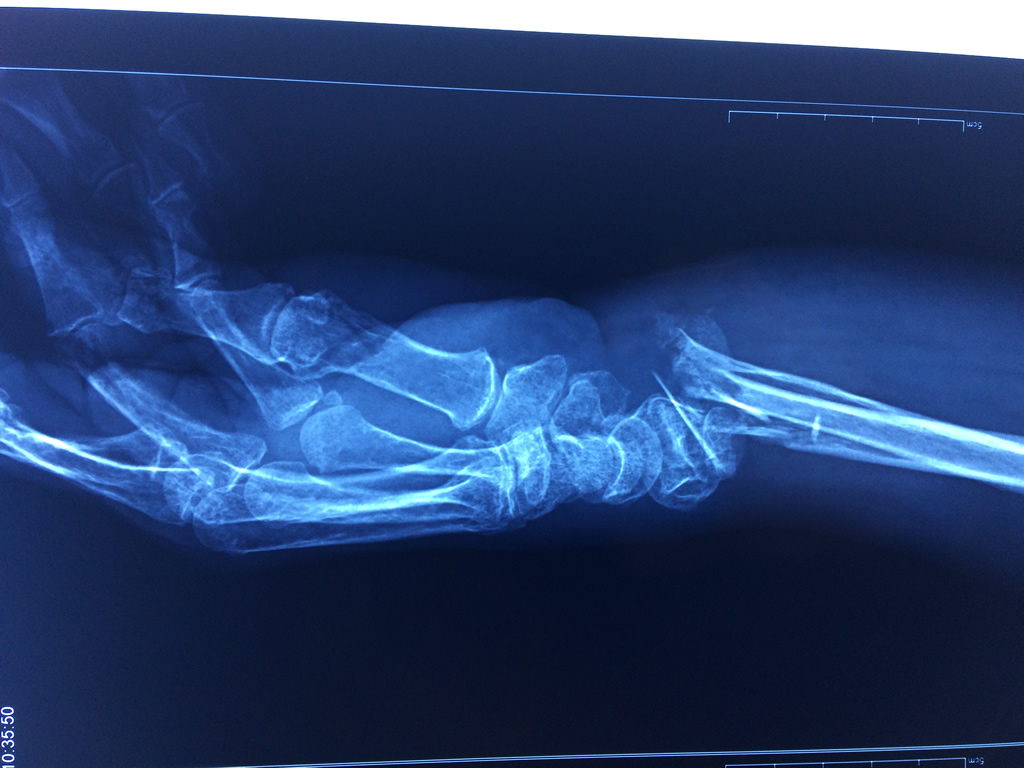

Cirugías de Calcaneo - Cirugías de Muñecas y Manos

Los procedimientos más comunes en cirugía de la mano son aquellos destinados a reparar traumatismos, incluyendo lesiones de tendones, nervios, vasos sanguíneos, y articulaciones; huesos fracturados; y quemaduras, cortes, y otros daños de la piel.